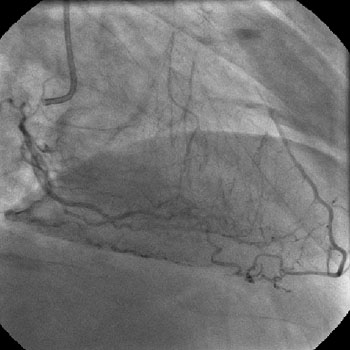

The left system was engaged with XB 3.5 guiding catheter through the femoral route. With the help of a 1.1x1.5mm CTO balloon, we directed a Shinobi guidewire towards the ostial LAD lesion (Figure 4). After making sure that the guidewire was pointing towards the CTO with its tip at the CTO lesion, we used the torquer to gently twirl the guidewire without forcing or overly manipulating it and allowed the guidewire to find its own way through the CTO by patiently twirling it at the lesion site. Within a few minutes, the guidewire jumped through the CTO lesion (Figure 5) and then through the lesion with the help of the CTO balloon (Figure 6). The path was first confirmed by engaging the RCA from the radial approach and injecting dye into the RCA (Figure 7). The CTO was then predilated with a 2.0x30mm Sapphire balloon (Figure 8 and Figure 9) and stented it with a 3.0x36mm DES (Figure 10 and Figure 11). Later the RCA was engaged with a JR 3.5 guiding catheter. A Cougar guidewire crossed the RCA lesion that was directly stented with a 3.0x13mm BMS (Figure 12 and Figure 13).

No residual stenosis found, TIMI III flow achieved distal to the lesion.